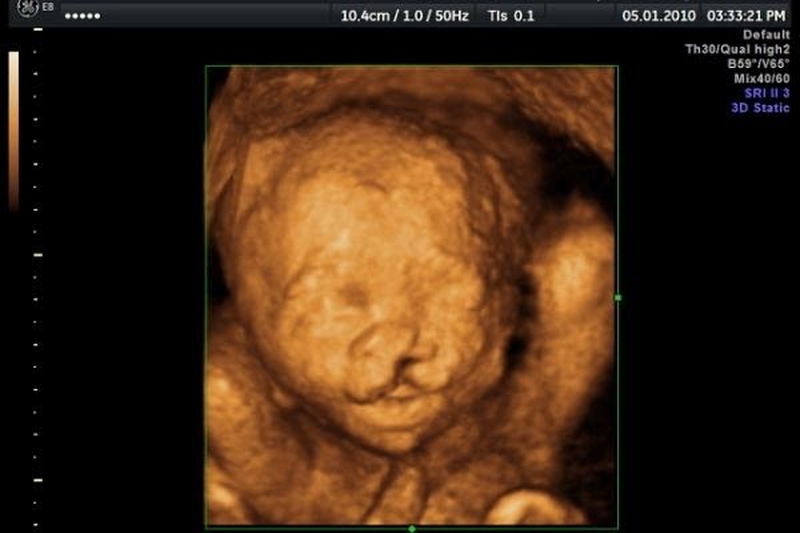

• Xét nghiệm NIPT từ tuần thứ 9 là tốt nhất để phát hiện sớm các nguy cơ dị tật bẩm sinh ở thai nhi, hơn nữa lúc này tỷ lệ DNA trong thai nhi đã đạt vừa đủ ở mức tiêu chuẩn để có kết quả tốt nhất.

Xét nghiệm nipt từ tuần bao nhiêu là tốt nhất? 1 Xét nghiệm NIPT từ tuần bao nhiêu để có kết quả chính xác nhất?

Xét nghiệm nipt từ tuần bao nhiêu là tốt nhất? 2 Xét nghiệm sàng lọc dị tật trước khi sinh là một điều vô cùng quan trọng.

Xét nghiệm nipt từ tuần bao nhiêu là tốt nhất? 3 Phát hiện sớm các dị tật bất thường ở trẻ để bác sĩ có hướng tư vấn và xử lý.